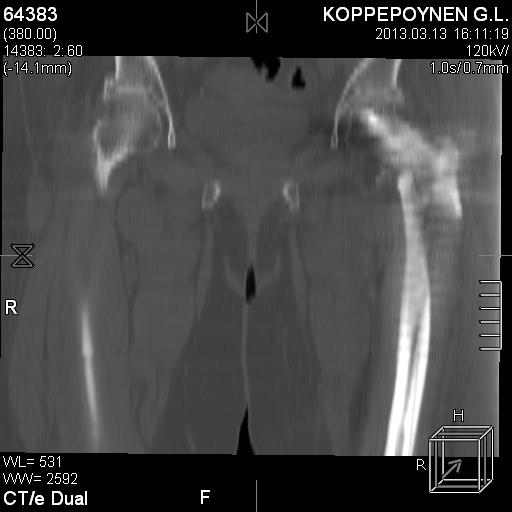

Делали КТ после операции.

|

Непонятно, на какой вопрос с помощью КТ хотели получить ответ? IMHO это было ненужное исследование, все проблемы были видны на обычном снимке. А что на второй проекции? Где аксиальная или профиль?

есть КТ после операции. у пациентки направление введения стержня совпадает с направлением большого вертела, однако большой вертел расколот на 2 отломка. Задний отломок лежит по оси, передний отломом "отошел" и создается впечатление неправильного введения стержня. Динамизации у пациентки не было... Привезут снимки после операции, скину